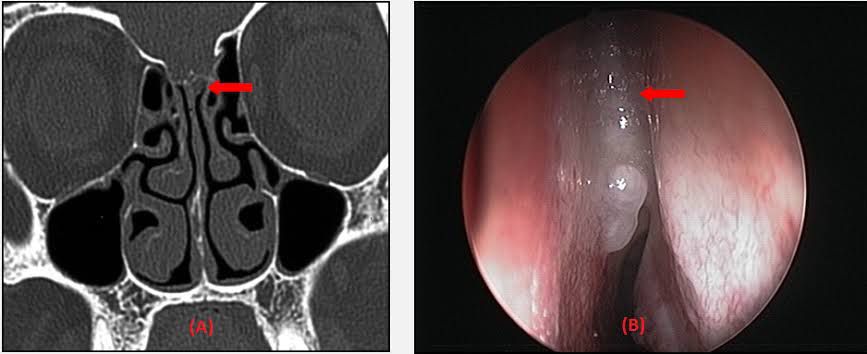

A cerebrospinal fluid (CSF) rhinorrhoea occurs when there is a fistula between the dura and the skull base and discharge of CSF from the nose. CSF rhinorrhea or liquorrhoea commonly occurs following head trauma (fronto-basal skull fractures), as a result of intracranial surgery, or destruction lesions.